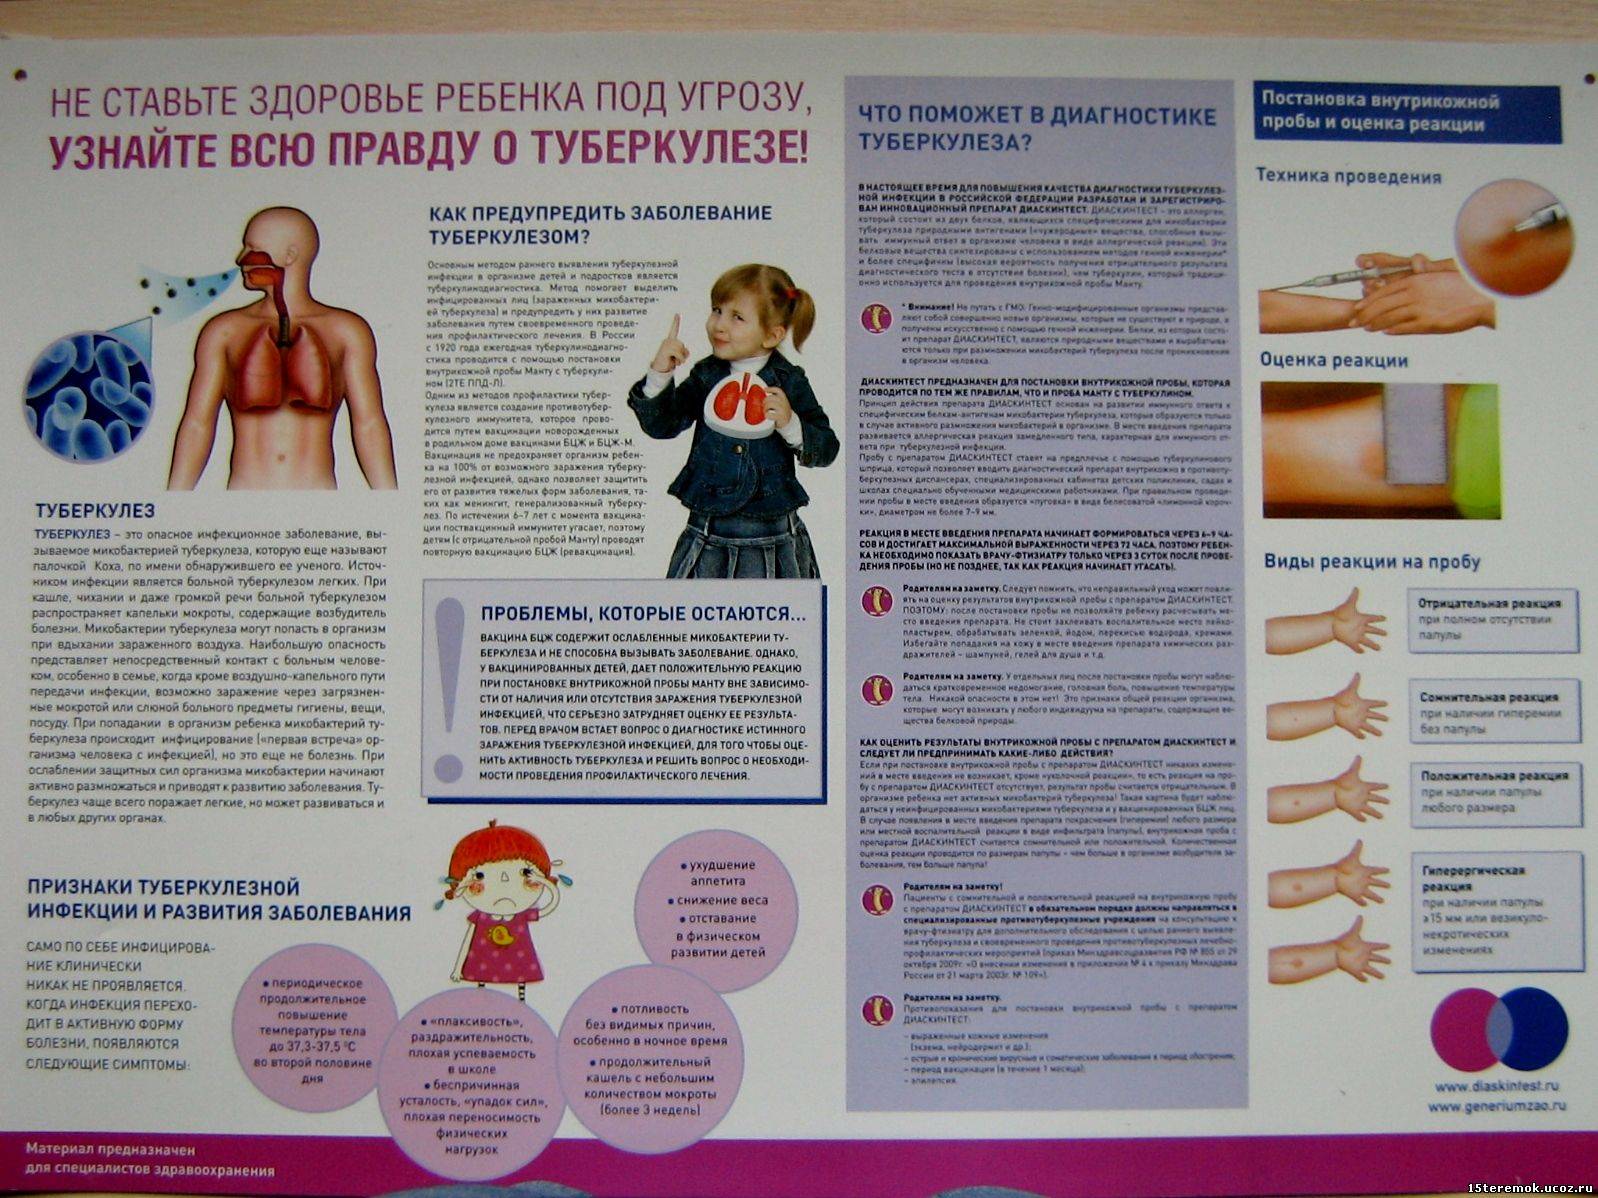

Симптомы и признаки туберкулеза: как распознать заболевание

Раздел: Визуальные уроки